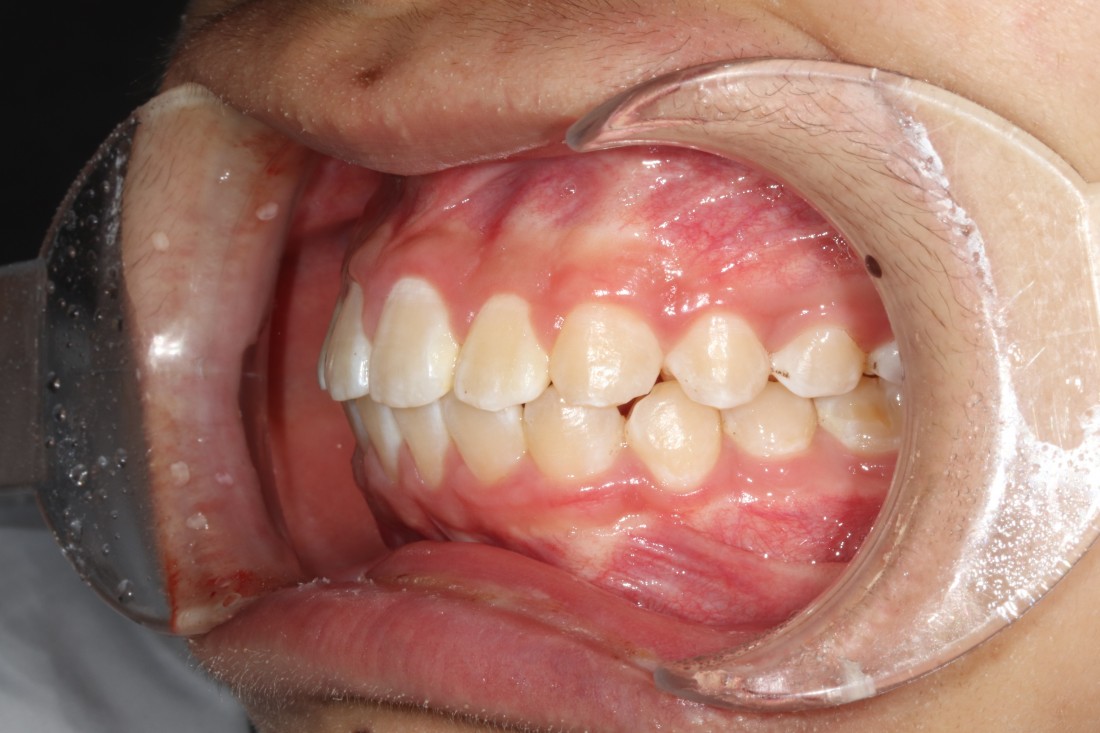

광산구 교정치과는

교정진료만을 담당하는

교정전담 의료진이 상주하고 있어서

전문적인 교정진료를 제공하며,

VIP 1인 룸 교정진료실을 운영하여

오직 단 한 분만을 위해 준비된

프라이빗 교정진료 공간을

준비해놓았습니다.